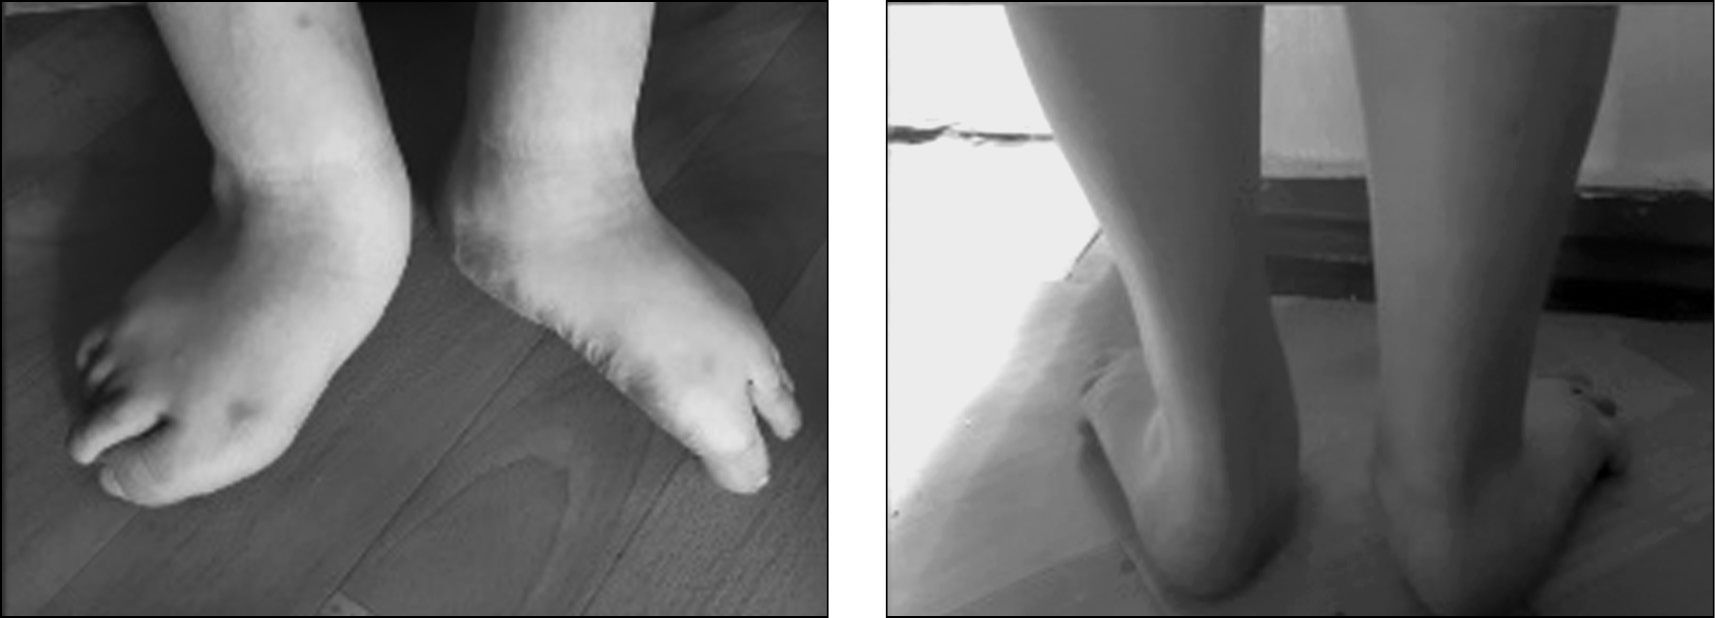

При отсутствии лечения при ВВТ (рис. 1), с увеличением массы тела, человека ожидают боли в стопах, инвалидность и сложности с подбором обуви. Как правило, страдает походка, что связанно с трудностями балансирования. Отмечается специфическое снашивание обуви. Боль в стопе часто развивается уже в раннем подростковом возрасте. Поскольку пяточные кости подтянуты, у пациента страдает фаза опоры в биомеханике ходьбы, а именно подфазы начального контакта (касание пяткой поверхности опоры) и окончание опоры (активное отталкивание).

Рис. 1. Пациент П., 17 лет. Врожденный вертикальный таран. Лечение в грудном возрасте гипсовыми повязками по месту жительства, без оперативного вмешательства

Fig. 1. Patient P., 17 years old. Vertical talus. Treatment in infancy with plaster casts at the place of residence, without surgery

У пациентов с ВВТ без лечения опорой служит средний отдел стопы, больше за счет внутреннего края, являющегося в норме продольным сводом и отвечающего за амортизирующую функцию при ходьбе и в положении стоя (рис. 2). Формируются болезненные натоптыши, мозоли и слизистые сумки, страдает сосудисто-нервный медиальный пучок [1, 22].